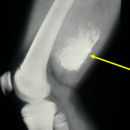

Radiographic imaging is used to help form a diagnosis. These include X-Ray, MRI, CT and Bone Scans.

An example of an Mesenchymal Chondrosarcoma MRI is shown.